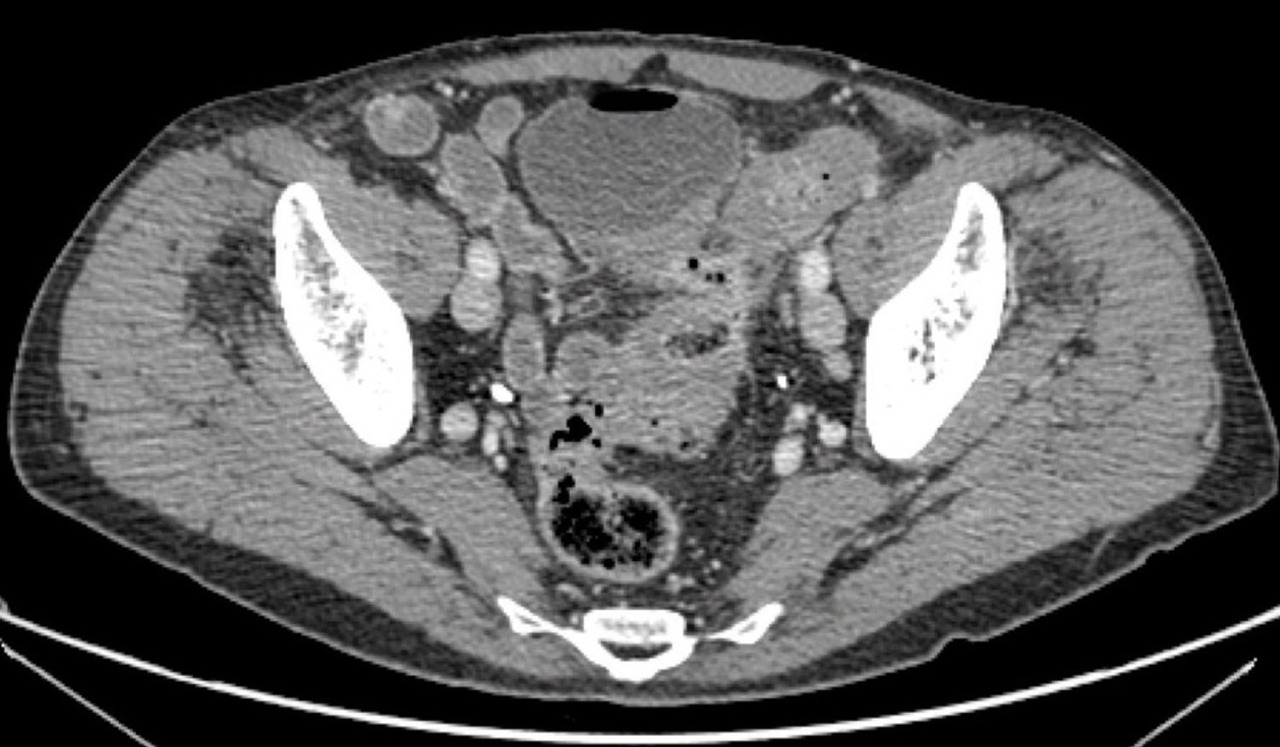

Il s’agit d’une fistule sigmoïdo-vésicale, avec présence d’air dans la vessie. Les fistules représentent 5 à 9 % des indications chirurgicales pour diverticulite sigmoïdienne compliquée. Elles correspondent au drainage du processus infectieux dans un organe de voisinage (vessie, rectum, intestin grêle, vagin, utérus) ou à l’extérieur vers la peau. Les fistules sigmoïdiennes d’origine diverticulaire peuvent compliquer le drainage percutané d’un abcès. Les plus fréquentes sont les fistules sigmoïdo-vésicales, comme dans cet exemple, qui représentent plus de 50 % des fistules. Elles surviennent préférentiellement chez l’homme ou chez la femme hystérectomisée. L’évolution naturelle avec drainage de la suppuration dans un organe creux permet en général une prise en charge chirurgicale en 1 temps avec résection sigmoïdienne et anastomose colorectale immédiate associée à la fermeture de la fistule. L’indication opératoire est formelle compte tenu du risque infectieux lié à la persistance de la fistule. L’intervention peut être réalisée par laparoscopie. En cas de dissection difficile ou de nécessité de réaliser une anastomose sous-douglassienne, certaines équipes préconisent la confection d’une stomie de protection.